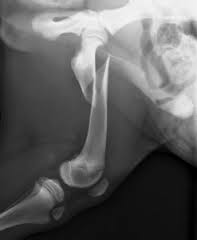

FRACTURA HELICOIDAL DE TERCIO PROXIMAL DE FÉMUR